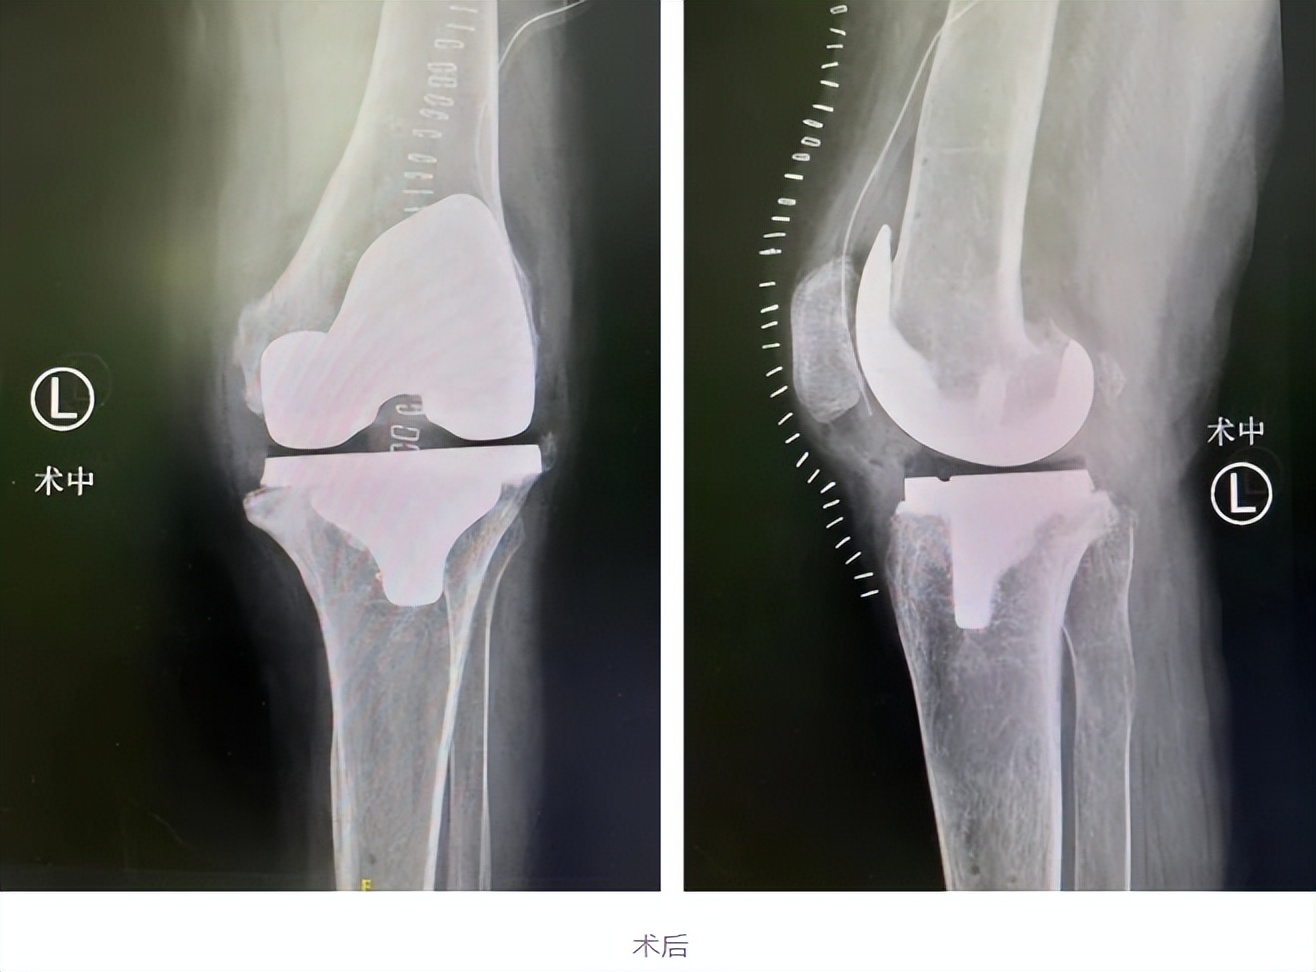

在结合相关资料及术前讨论后,仁慈关节外科张传开、郝亮、王琳、蒋涛手术团队为李大姐在Mako关节置换机器人导航下行左侧人工膝关节置换术。

术前,Mako机器人基于CT进行3D的智能建模,根据患者实际情况个性化定制手术方案。同时,在术中实时根据患者具体软组织张力进行动态调整,辅助手术医生进行精准化、个性化的手术操作。尤其是对截骨、假体安装等重要环节,都进行了全程三维定位,实时将角度、大小、骨质覆盖等重要信息通过数字影像及时传达给手术医生,帮助医生做出准确判断,将手术精度控制在毫米级,完美实现了“精准手术”的要求。